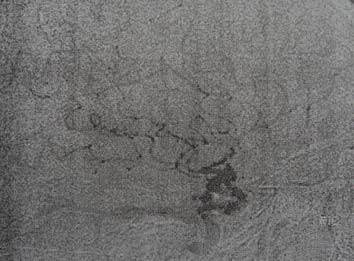

Petunjuk: Seorang laki-laki usia 16 tahun dengan hasil MRI sebagaimana ditunjukkan di bawah ini, dirujuk ke kantor anda. Hasil pemeriksaan laboratorium pasien mengungkapkan bahwa dia menderita hipotirodisme, kekurangan kortisol dan kadar prolaktin sebesar 69. Keluarganya mengatakan bahwa mereka mencatat adanya berbagai perubahan perilaku dan baru-baru ini mengalami kenaikan berat badan. Mata kirinya tidak bisa melihat dan lapang pandangan temporal mata kanannya terputus.

C. Kraniofaringioma

PERTANYAAN 44 - 45

Petunjuk: Seorang laki-laki usia 16 tahun dengan hasil MRI sebagaimana ditunjukkan di bawah ini, dirujuk ke kantor anda. Hasil pemeriksaan laboratorium pasien mengungkapkan bahwa dia menderita hipotirodisme, kekurangan kortisol dan kadar prolaktin sebesar 69. Keluarganya mengatakan bahwa mereka mencatat

adanya berbagai perubahan perilaku dan baru-baru ini mengalami kenaikan berat badan. Mata kirinya tidak bisa melihat dan lapang pandangan temporal mata kanannya terputus.

B. Efek Stalk